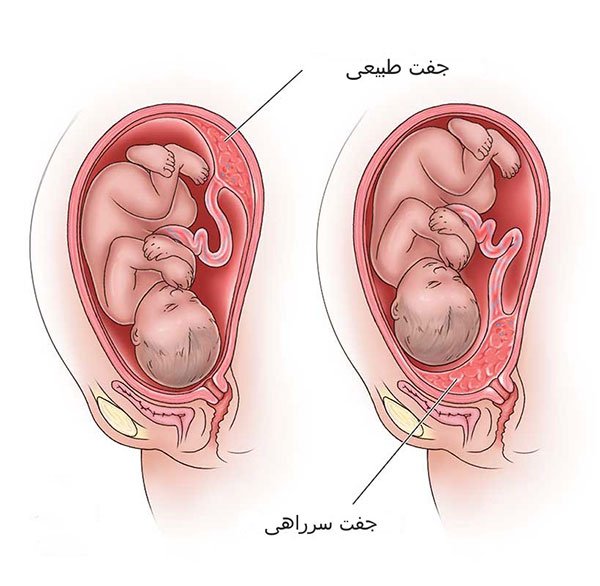

-جفت سرراهی: هنگامی که جفت در پایین رحم قرار دارد، ممکن است تا حدی یا به طور کامل دهانه رحم را بپوشاند. این جفت سرراهی نامیده می شود. ممکن است باعث خونریزی واژینال شود. این نوع خونریزی اغلب بدون درد اتفاق می افتد. برخی از انواع جفت سرراهی در هفته 32 تا 35 بارداری با کشیده شدن و نازک شدن قسمت پایینی رحم، خود به خود برطرف می شوند و پس از آن سیر لیبر و زایمان می تواند به طور معمول اتفاق بیفتد. اگر جفت سرراهی برطرف نشد، ممکن است نیاز به زایمان سزارین داشته باشید

جفت سرراهی: وضعیتی که در آن جفت دهانه رحم را می پوشاند.